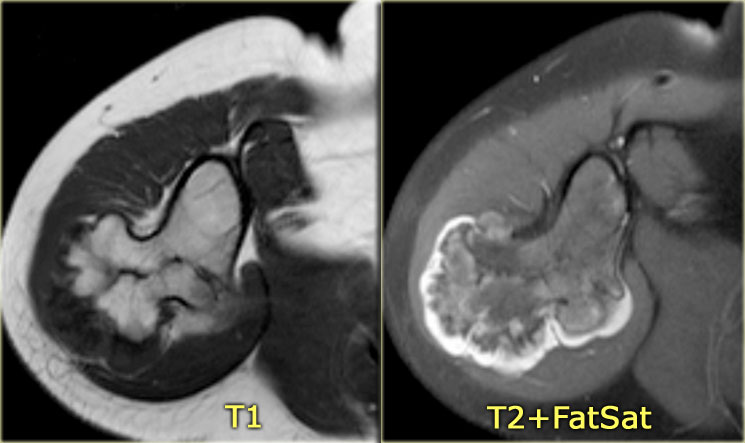

ABC (8)

On the left another ABC, located in the distal femur.

The plain radiograph shows a layered periosteal reaction and Codman triangle in direct relationship to an expansile lytic lesion with a thin peripheral bone shell.

CT also reveals the subperiosteal origin of the lesion with secondary involvement of the cortical bone.

Axial T2-weighted image with fatsat and contrast enhanced T1-weighted image with fat sat show multiple fluid-fluid levels with rim enhancement of the cavities filled with blood.

This is typical for an aneurysmal bone cyst.